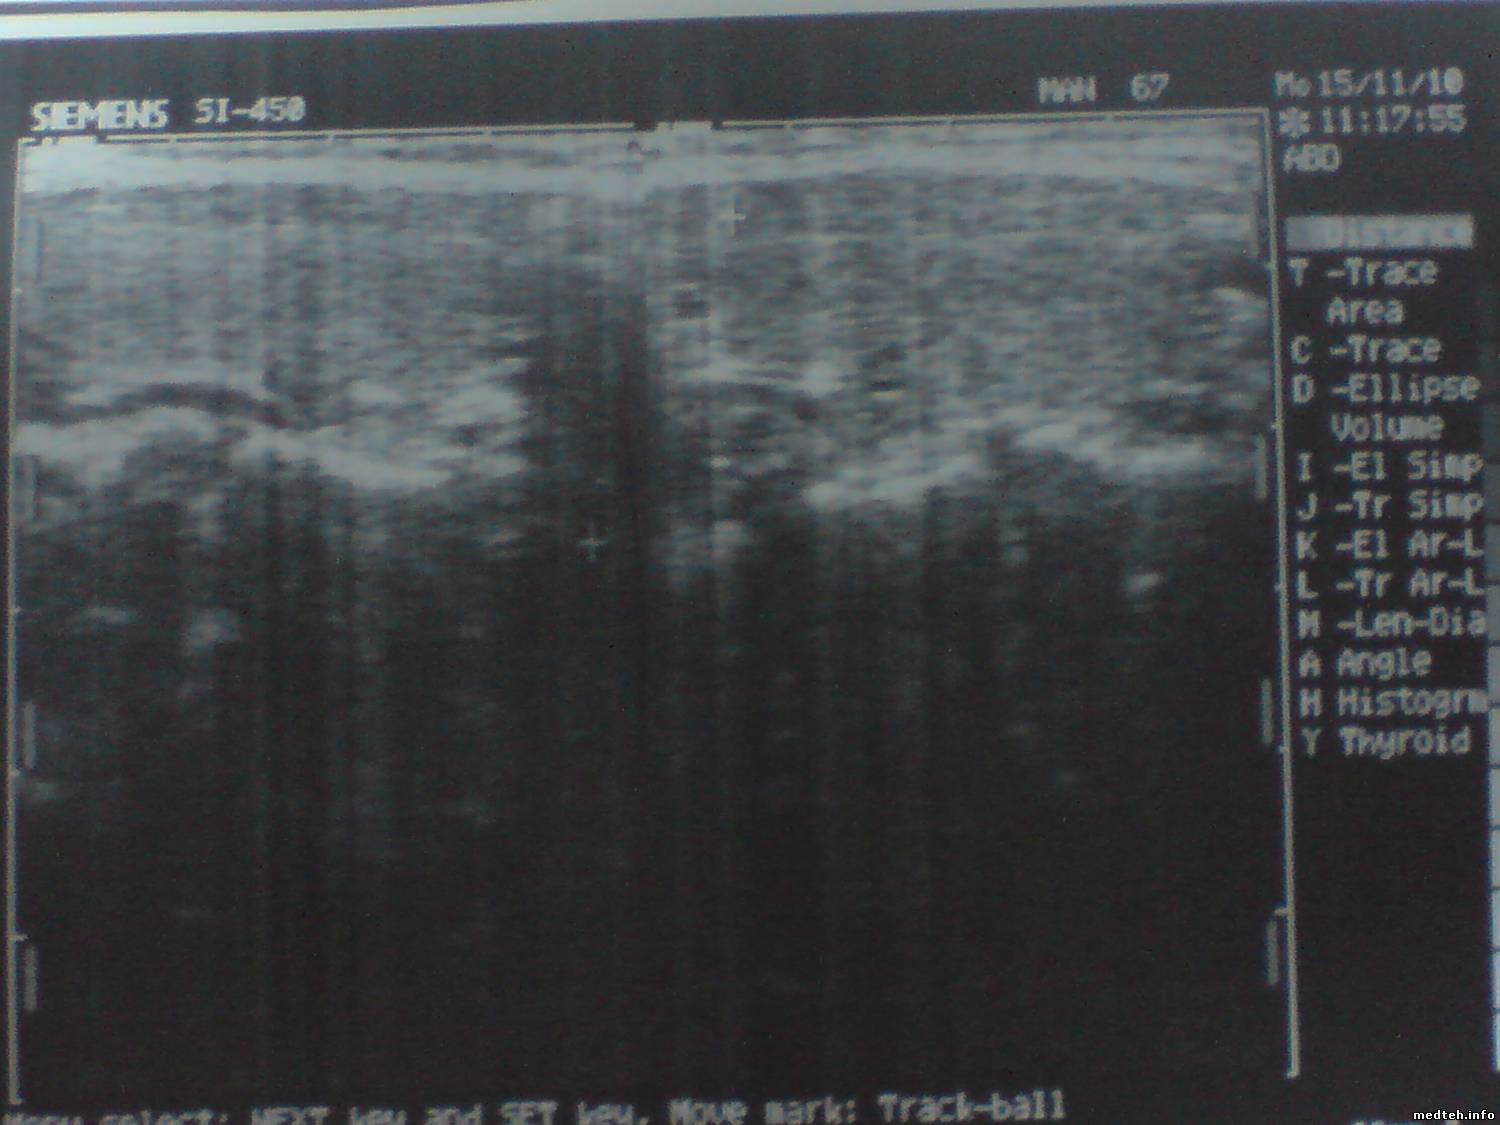

Проблема в том, что с настройками по умолчанию доктору не нравится изображение органов (не чёткие контура). Хотя аппарату 16 лет и может датчики уже не "тянут".

Может кто визуально определит и подскажет по фоткам чем можно поиграть в настройках.

Собственно говоря, в аппарате нечего настраивать. Корреляция, частота кадров (frame rate), пост-процесс. Если нет четкости ни на одном из датчиков,- проблемы с аппаратом. Если выбран адекватный пресет, картинка должна быть удовлетворительной. Сколько этих систем знаю, ни разу не слышал подобных жалоб. Единственный момент - картинка на линейке 7,5 МГЦ действительно не очень, ни в какое сравнение с нынешними системами не идет.

Датчиком которым смотрит щитовидку - изображение удволитворительное а

тут какраз и проблема.Посмотрите - есть снимки

На всех изображениях вертикальные размытые полосы, которые накладываются на полезный сигнал в видеоусилителе монитора - барахлит сам видеоусилитель или его питание. Плюс старый подсевший кинескоп и разрегулировка фокуса.

А вертикальные размытые полосы это на экране или только на снимках - дефект печати?

Похоже все-таки на печать :)

То, что я вижу,- это снимки снимков с принтера. И это дефекты самого принтера, а никак не аппарата, нужно фото именно с экрана, и с хорошим качеством, без фспышки. Тогда можно будет о чем-то говорить.

Размытость контуров может давать CL3 (корреляция). Попробуйте уменьшить.